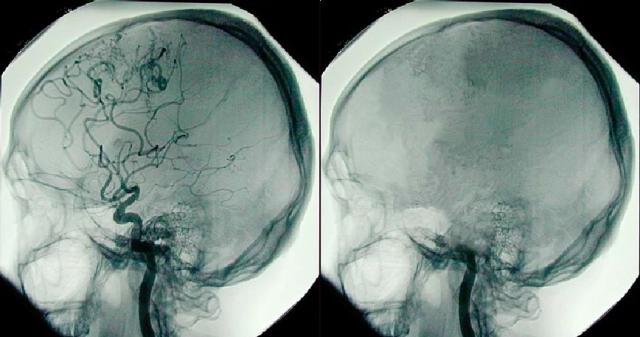

这张照片展示了左侧脑部血管造影,显示有血流;右侧脑部没有血流,就像脑死亡患者那样。© Sparkman Media

脑血管造影显示的椎基底动脉和后脑血液循环前 / 后供血情况,以及威利氏环及其一条供应血管的后视图。© Sparkman Media